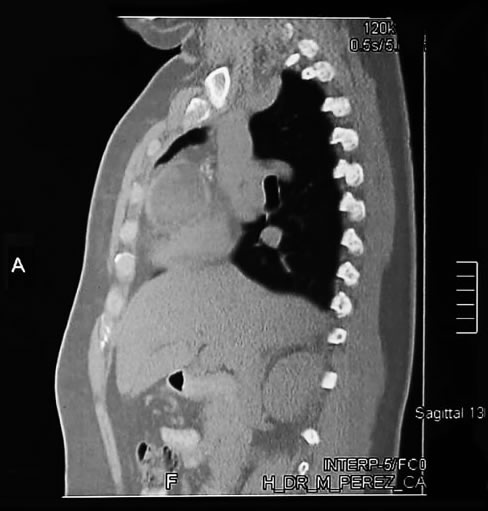

Corte Sagital hileo pulmonar derecho

La misma imagen o corte superior demuestra que la lesión es encapsulada de contenido  heterogéneo y con  nódulo calcificado en su interior, demuestra su relación a los vasos del hileo pulmonar derecho posterior sin invadirlos.

Corte Sagital vena cava superior

El mismo corte sagital a nivel de la cava superior, demuestra la imagen en su mayor diámetro, de contenido solido, por su cápsula de aspecto brillante sin trabéculas ni tabiques en su interior.